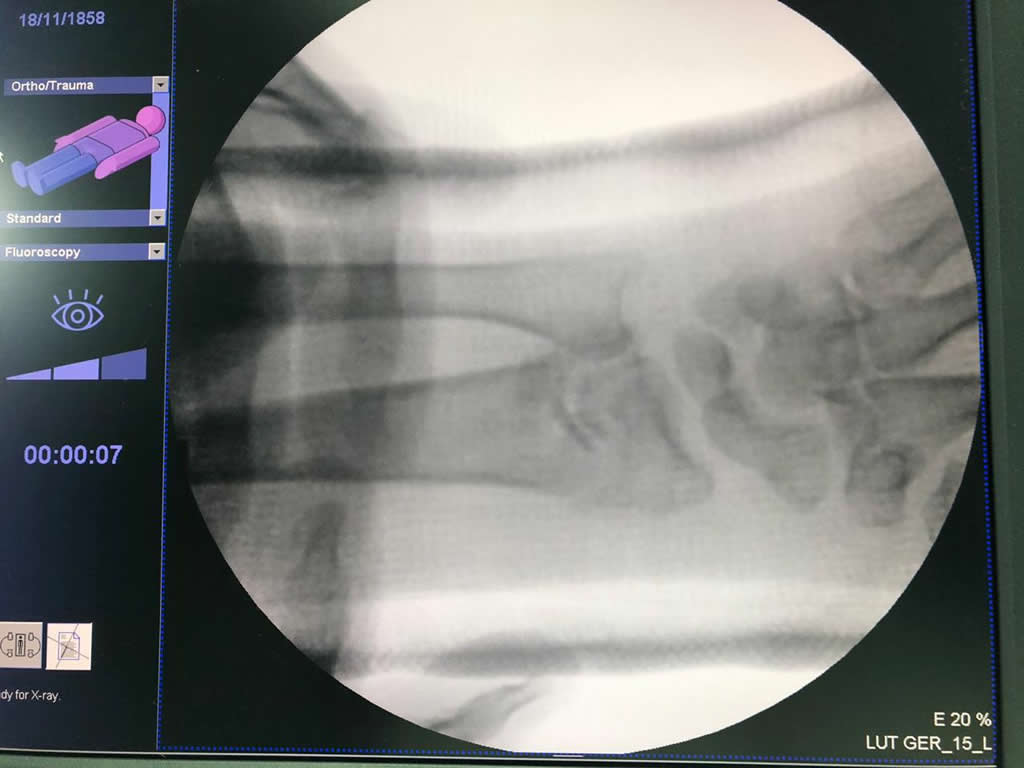

Cirugías de Húmero - Cirugías de Muñecas y Manos

Los procedimientos más comunes en cirugía de la mano son aquellos destinados a reparar traumatismos, incluyendo lesiones de tendones, nervios, vasos sanguíneos, y articulaciones; huesos fracturados; y quemaduras, cortes, y otros daños de la piel.